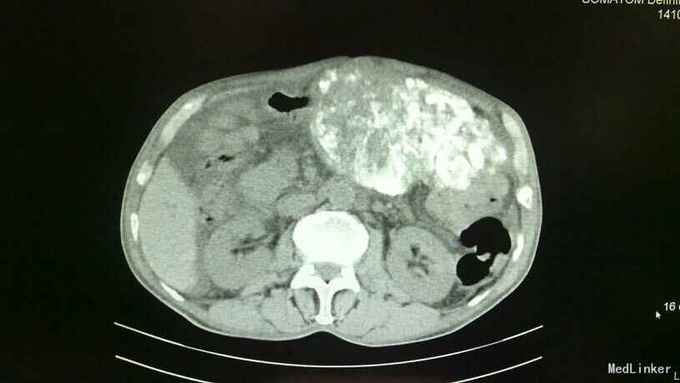

诊断:1、原发性肝细胞癌(巨块型) 2、肝内转移并子灶形成 3、低蛋白血症 4、胸、腹腔积液(少量) 治疗:入院后完善相关常规、生化检查如上述,综合评估病情后考虑患者巨块型肝癌大小约达30*13cm,存在肝癌肿块破裂大出血风险可能性极大,遂立即向其家属告病重。治疗上予护肝、补充白蛋白、护心、补液等对症支持治疗,3日后送手术室行”肝癌血管介入化疗栓塞术(TACE术)“,术中先选取肝动脉,予”氟脲苷+卡铂+平阳霉素+丝裂霉素“向血管行灌注化疗,再予碘化油向血管内灌注以栓塞血管阻断肿瘤血供,再选取肠系膜上动脉,再予上述化疗药物向血管内行灌注化疗。术后患者出现上腹部疼痛、腹胀,食欲严重下降,发热,呈中高热,呕吐数次。均考虑患者介入术后常见不良反应及肝脏及肿块栓塞后液化坏死所致。术后常规予抗感染、护肝、护胃、护心、止呕、补蛋白、适当利尿、维持电解质平衡、加强护理、记24小时尿量等对症支持治疗。病情好转并稳定后复查上腹部CT较入院时缩小,具体见下图所示,提示治疗有效。

随访:随访一月,患者肝左叶巨块型肝癌较前缩小。查体触诊上中腹部可及一肿块大小约24*8cm,于剑突下8cm可触及,于右侧肝肋缘中点下2cm处可触及,质地硬,边缘不规整,表面凹凸不平。 讨论:TACE术:是指将导管选择性或超选择性插入到肿瘤供血靶动脉后,以适当的速度注入适量的栓塞剂,使靶动脉闭塞,引起肿瘤组织的缺血坏死。使用抗癌药物或药物微球进行栓塞可起到化疗性栓塞的作用,称之为TACE。目前最多用于肝癌的治疗,包括: 肝动脉插管化疗栓塞,或肝动脉插管化疗灌注。我们都知道:肿瘤的生长有赖于肿瘤新生血管的形成,当肿瘤生长至一定体积(1~2mm)时,由于缺氧和局部组织PH值的下降,肿瘤便会分泌促血管生成因子,加速肿瘤新生血管的形成,以提供肿瘤生长所需要的氧和营养成分。TACE作为临床治疗肝细胞癌的重要方法,主要通过栓塞肿瘤的供血动脉,阻断肿瘤的血供,导致肿瘤缺血、缺氧,达到抑制肿瘤生长、促使肿瘤细胞坏死、凋亡的目的。适用于原发性或转移性肝癌、肝癌术后复发(肝功能Child分级为A、B-级)、肝血管瘤、肾癌、盆腔肿瘤等的治疗以及鼻咽癌、肺癌、消化道、盆腔肿瘤大出血时的栓塞止血等。 特别是在此例中:患者为73岁高龄的老年患者,又是如此巨块型肝癌,大小约达30*13cm,已经不具备手术指征,因为手术风险性极大,极大可能会因为在术中各种原因导致肝癌破裂而大出血不止却无法抢救,甚至根本抢救不过来!或其他原因记其他不利因素,使得患者及其家属选择保守治疗的。而此时,TACE术就特别适用于这一类患者,既可以收到一定的疗效也可以缓解病情进展,延缓生命,改善生活质量。并且TACE术还可以按照这个原理扩展到其他的肿瘤类型,比如肺癌,直肠癌,妇科恶性肿瘤,胃癌等等,均可以尝试行动脉灌注化疗,亦可以称之为局部化疗。比起全身静脉化疗,此法可以使病灶(肿瘤)更局限更集中吸收化疗药,再辅以差价量化疗会取得不错的效果。